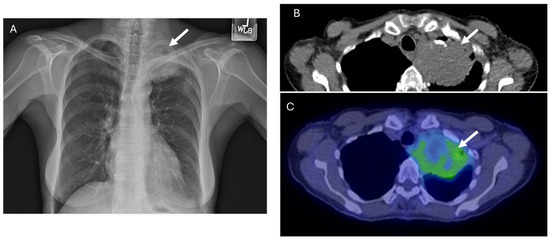

3.1. POEMS Syndrome

| POEMS Syndrome |